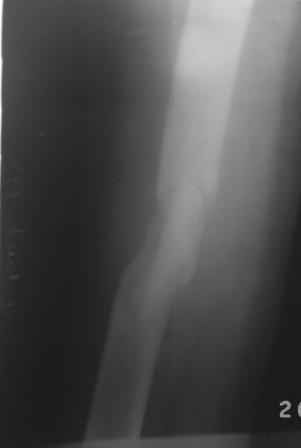

Добрый вечер, уважаемые коллеги. Произведена операция БИОС. Больной 35л, 3-месяца назад получил тяжелую сочетанную травму, после улучшение состояния доставлен к нам, Р-грамма прилагается.

Учитывая поворот большого костного осколка на 180гр. , произведена открытая репозиция, скелетирована только передне-наружная поверхность., антеградный и/м остеосинтез, и наш старенький ЭОП перестал работать, пришлось дистальную блокировку произвести в рентген кабинете под сериоскоп-Сименс, с большими трудностями.

И в конце выяснилось что имеется диастаз задне-внутренной стенки. Заново блокировать рентгенологи не разрешили.

Теперь что делать?

Наш план - динамизировать, в дистальном овальном отверстие имеется запас около 1см, но когда динамизировать?

Или имеется другие варианты?